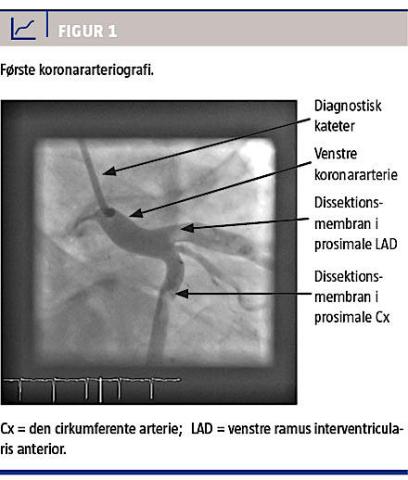

En kontrol-KAG efter fire måneder viste åbne stent uden tegn på instentrestenose eller frie dissektionsmembraner (Figur 2). Ved klinisk kontrol efter otte måneder var patienten i velbefindende og havde genoptaget sin træning, dog ikke karate. Den afsluttende ekkokardiografi viste normale forhold.